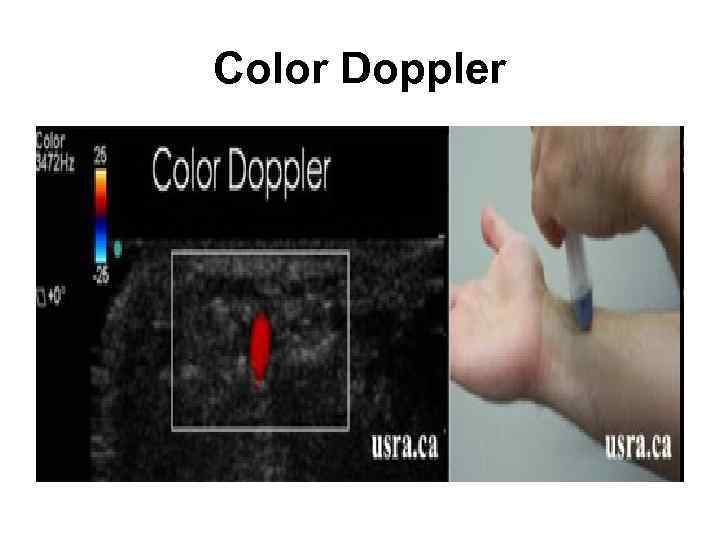

Цветовой допплер (Color Doppler)

Цветовой допплер (Color Doppler)

Color Doppler

Color Doppler

Color Doppler

Color Doppler

Color Doppler

Color Doppler

Цветовой допплер (Color Doppler) • выделение на эхограмме цветом (цветное картирование) характера кровотока в области интереса. • Кровоток к датчику принято картировать красным цветом, от датчика - синим цветом. • Турбулентный кровоток картируется сине-зеленожелтым цветом. • Цветовой допплер применяется для исследования кровотока в сосудах, в эхокардиографии.

Цветовой допплер (Color Doppler) • выделение на эхограмме цветом (цветное картирование) характера кровотока в области интереса. • Кровоток к датчику принято картировать красным цветом, от датчика - синим цветом. • Турбулентный кровоток картируется сине-зеленожелтым цветом. • Цветовой допплер применяется для исследования кровотока в сосудах, в эхокардиографии.

Цветовой допплер • Кровоток к датчику принято картировать красным цветом, • от датчика - синим цветом. • Турбулентный кровоток картируется сине-зелено-желтым цветом.

Цветовой допплер • Кровоток к датчику принято картировать красным цветом, • от датчика - синим цветом. • Турбулентный кровоток картируется сине-зелено-желтым цветом.